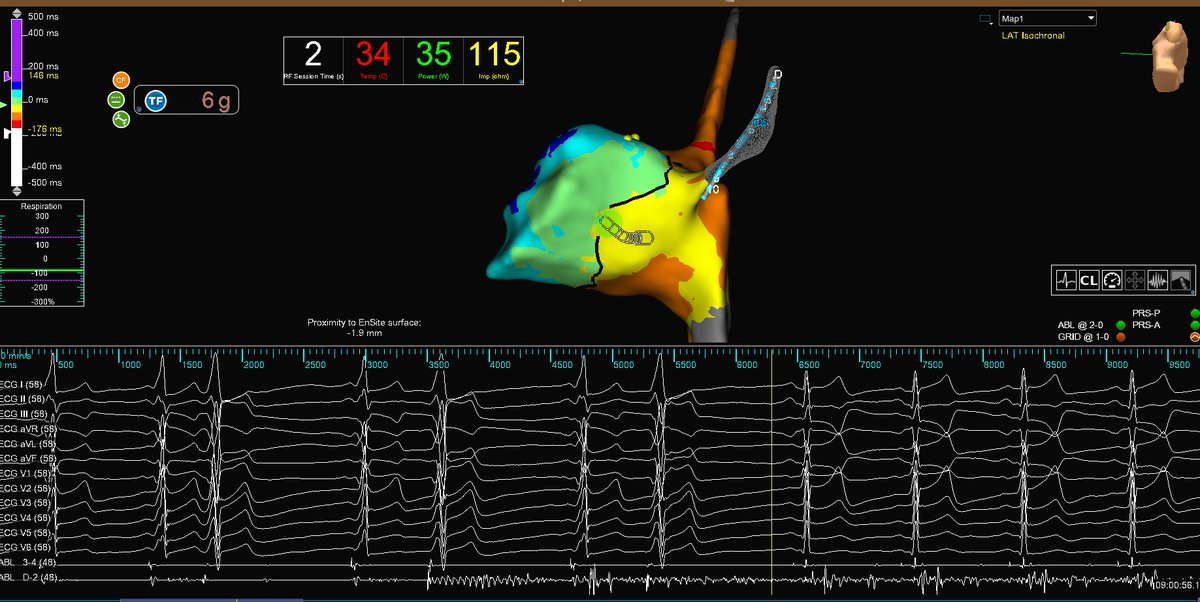

Micro-reentrant AT Mondays?!? Let's go! 🎯 Entire re-entrant circuit on the Grid EGMs imperceptible on recording system <0.06 mV Annotated automatically based on frequency w #OTNF One burn term 🔥🔥#MapMoreBurnLess @AbbottCardio

Entire re-entrant circuit on the Grid

EGMs imperceptible on recording system &amp;lt;0.06 mV

Annotated automatically based on frequency w #OTNF

One burn term 🔥🔥#MapMoreBurnLess